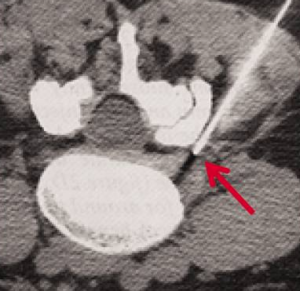

Attraverso l’Amplificatore di brillanza, l’ago è posizionato nel punto di uscita del nervo infiammato dal canale spinale, a pochi millimetri dall’ernia.

L’uso delle apparecchiature radiologiche permette di verificare in continuo l’accuratezza della metodica.

- La possibilità di trattare e documentare radiologicamente la diffusione di Ossigeno-Ozono evitando ogni complicanza.